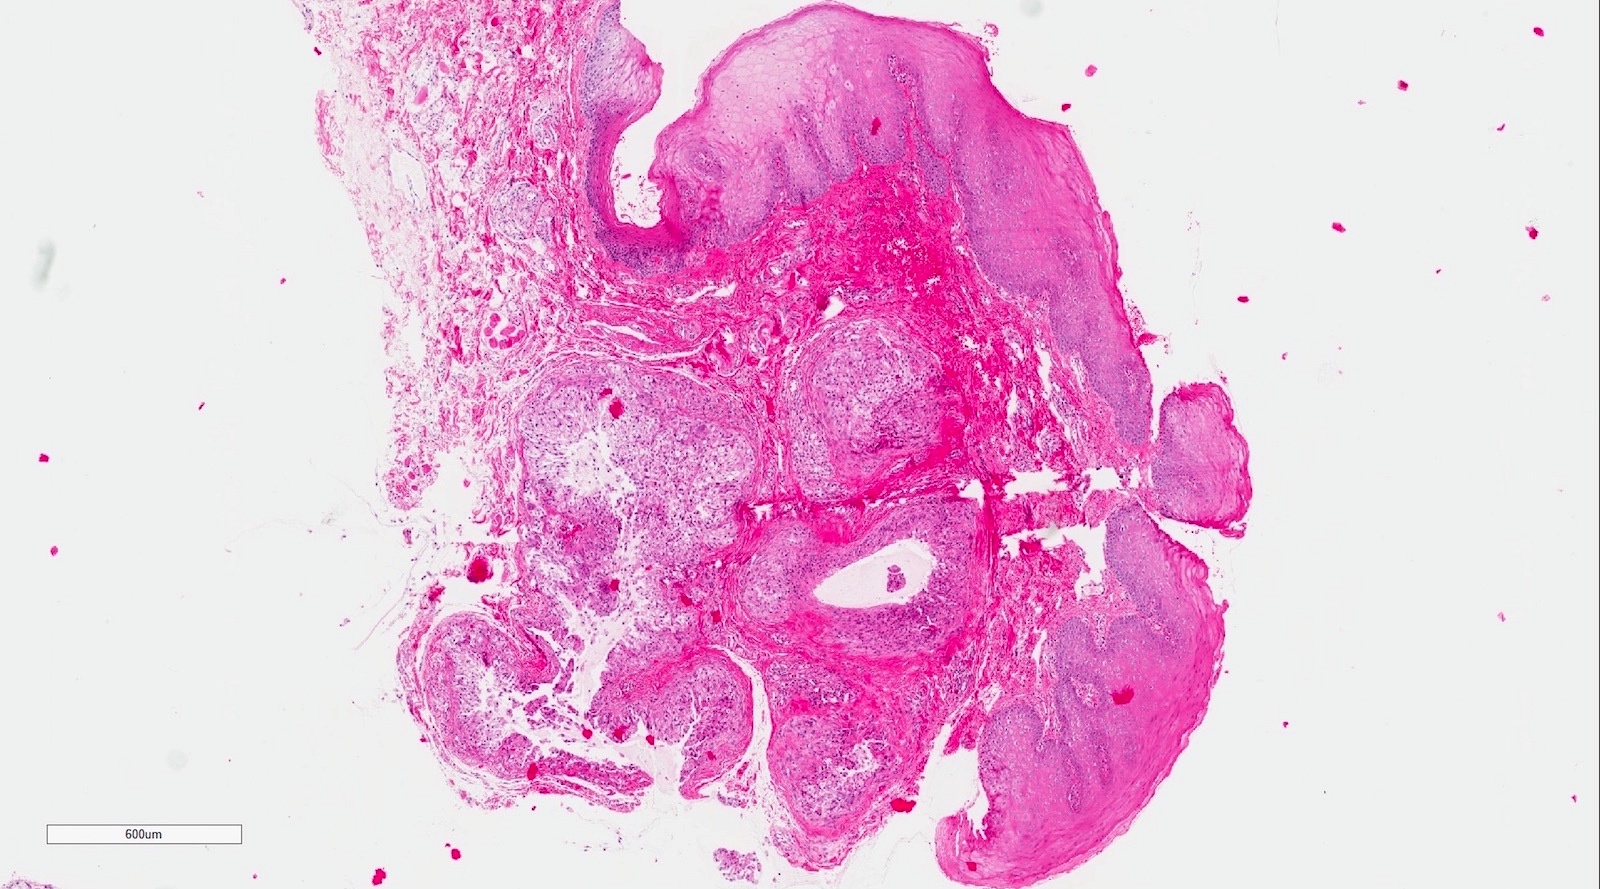

Microscopic (histologic) description

- If removed intact

- Pseudocyst cavity containing mucin, abundant epithelioid foamy histiocytes (muciphages), neutrophils and granulation tissue (Acta Histochem 2014;116:40)

- If removed ruptured

- Fragments of granulation tissue containing epithelioid foamy histiocytes (muciphages) and neutrophils, may see mucinous material (Acta Histochem 2014;116:40)

- Removed salivary gland parenchyma showing obstructive changes

- Acinar atrophy, ductal dilatation with periductal hyalinization, interstitial lymphoplasmacytic infiltrate and interstitial fibrosis at late stage (J Oral Maxillofac Surg 2008;66:2050)

- May see ruptured feeding salivary duct with squamous metaplasia (J Oral Maxillofac Surg 2008;66:2050)

- Long standing lesions organize into fibrosis resembling a fibroepithelial polyp (Acta Histochem 2014;116:40)

- No epithelial cyst lining, may see overlying surface oral mucosa with variable atrophy in superficial mucoceles (J Oral Maxillofac Surg 2011;69:1086)

Microscopic (histologic) images